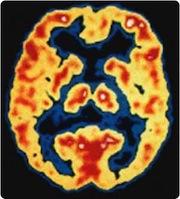

October 19, 2011 – The development of Alzheimer’s disease drugs and early detection has been hindered for years because no imaging agents or diagnostic tests existed. The only definitive way to diagnosis the disease was through cadaver brain biopsy samples. However, new radiotracers have been developed to illuminate the beta amyloid plaques that accumulate in specific areas of the brain in Alzheimer’s patients.

Using positron emission tomography (PET) and the radiotracer 11-C Pittsburgh Compound B (PIB), Roche said treatment with its drug candidate monoclonal antibody gantenerumab showed amyloid decrease in the brain of Alzheimer patients. This is the objective of the SCarlet RoAD trial, which will investigate the efficacy and safety of gantenerumab in patients in the early or prodromal stage of Alzheimer's disease.

The study used gantenerumab at two different doses or placebo. Brain amyloid was measured in 16 patients with mild to moderate Alzheimer's disease using PET and PIB. Alzheimer's disease brain slices from an independent patient sample were incubated with gantenerumab at increasing concentrations and with human microglia in an ex vivo phagocytosis assay.

Results from Phase I clinical trials and ex vivo studies demonstrated that gantenerumab treatment results in a dose-dependent reduction of brain amyloid, possibly through phagocytosis via brain microglial cells. Amyloid load increased in patients receiving placebo treatment.